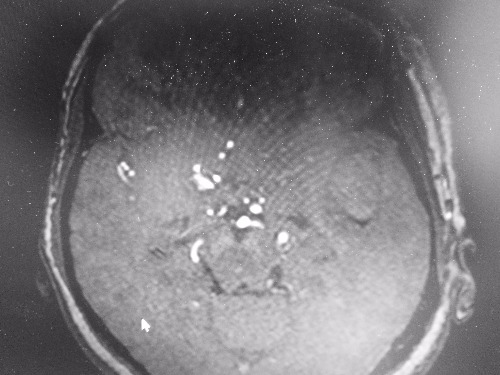

MRI7237:烟雾病

两例病人分别为脑梗塞和出血

右侧颈内动脉上端、右侧大脑中动脉闭塞,考虑烟雾病。

患者年龄,右侧颈内动脉闭塞。烟雾病?